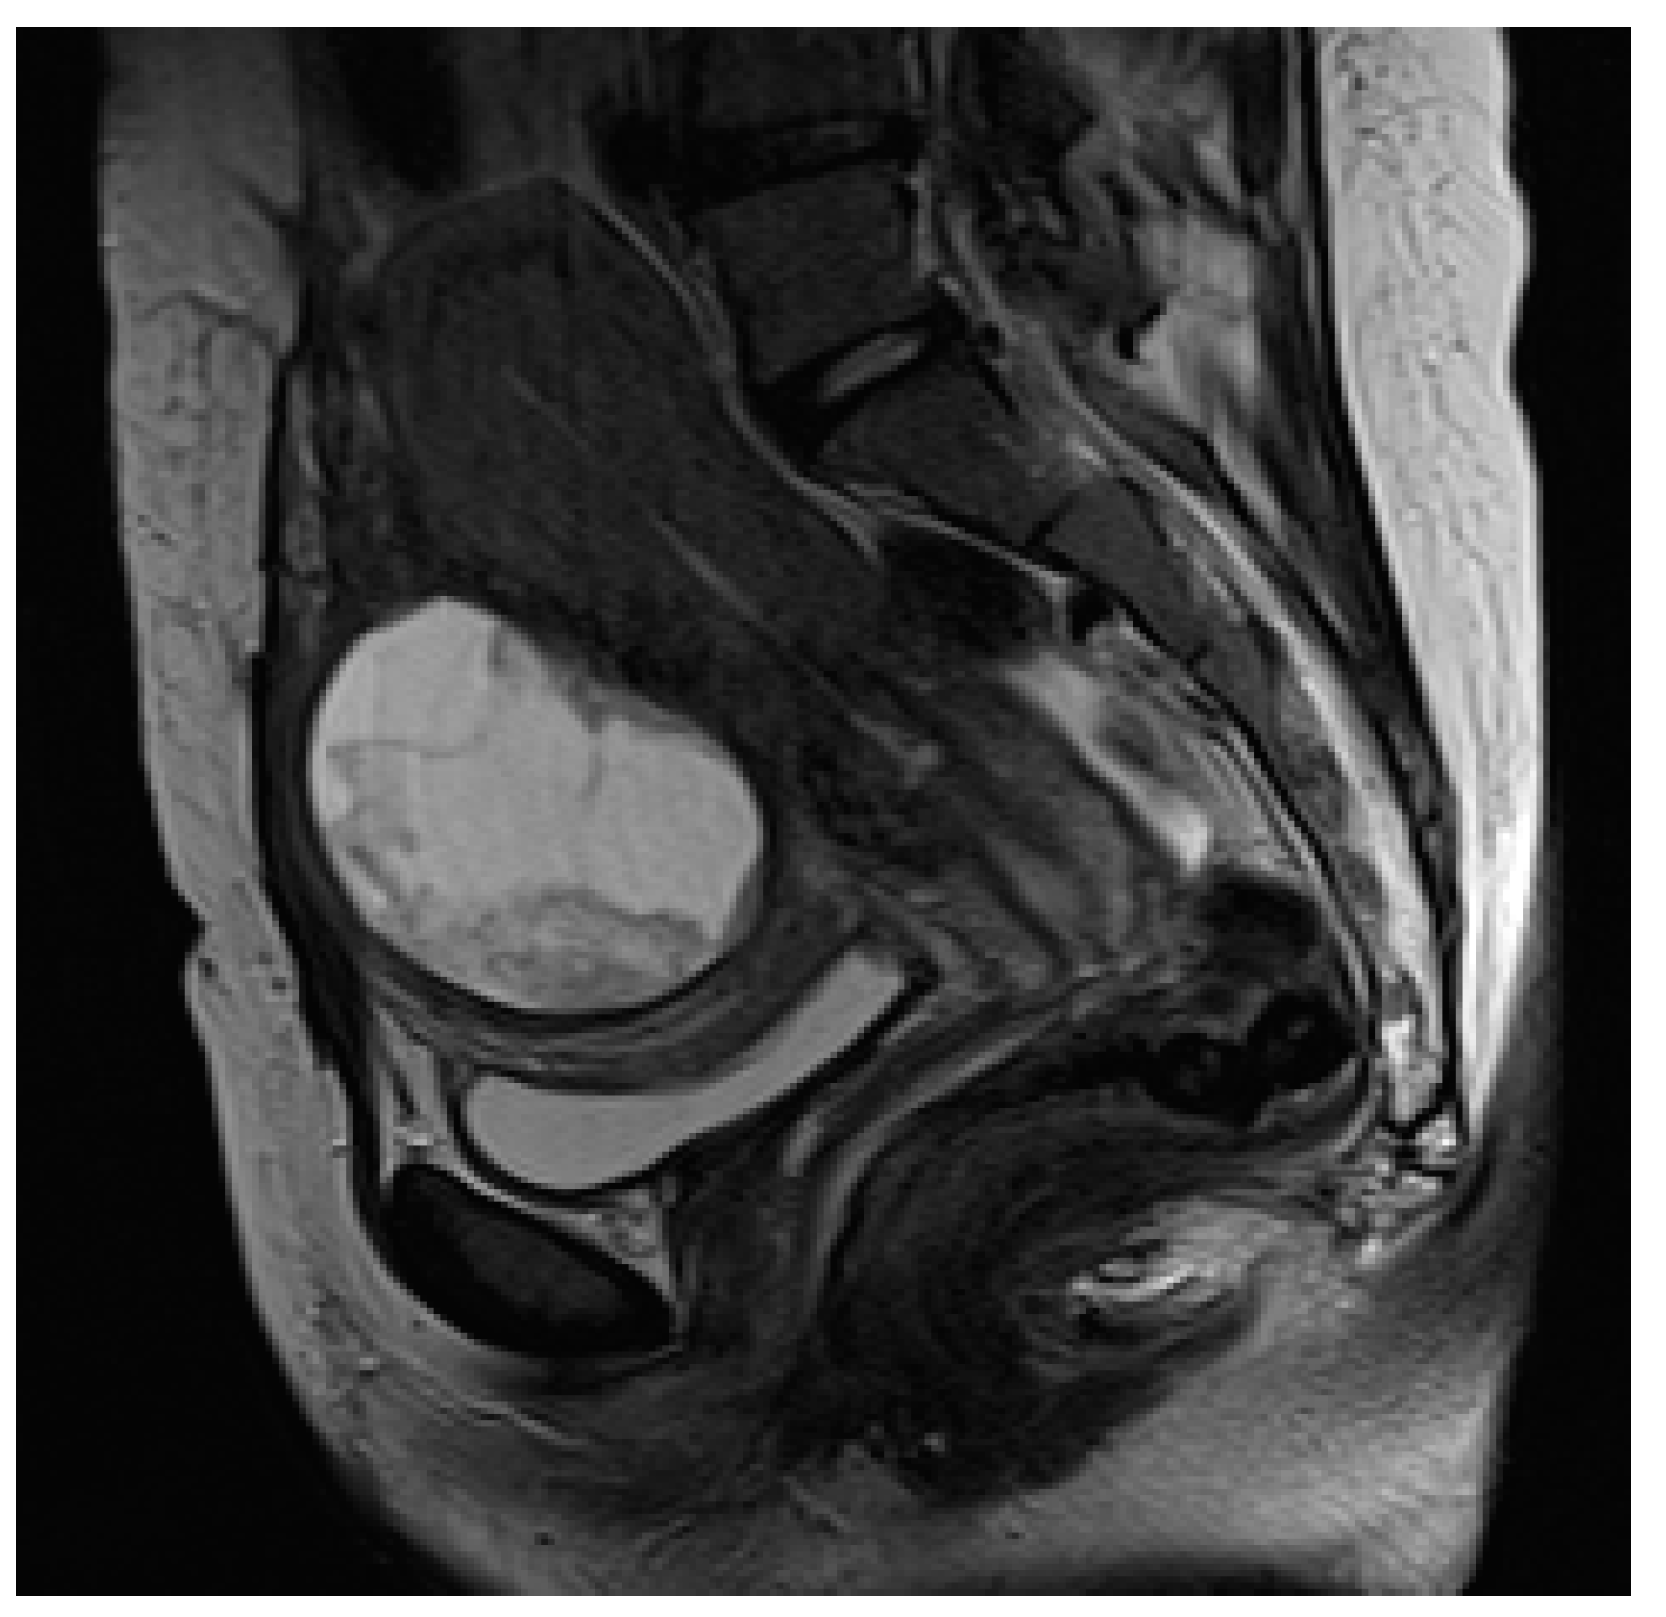

MRI allows for the detection and characterization of large bladder flap hematomas (>4 cm in size) associated with UR or more often with UD (Figure 6).

Figure 6. Puerperal patient, 34 years old, on the 14th day after caesarean section. Sagittal T2-weighted sequence shows large bladder flap hematoma (6.5 cm in maximum diameter), resulting from uterine dehiscence at the incision site and located between low uterine segment and bladder wall.